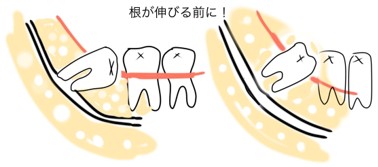

親知らずの根は、一般的に18〜25歳で完成するといわれています。親知らずの根の先が神経に到達する前の若いうちの抜歯は、神経損傷、麻痺のリスクが軽減されるので、検討してみてはいかがでしょうか。

お口の中が非常にキレイに磨かれていて、今後、親知らずが虫歯や歯周病になる可能性は低いですが、まずは親知らずの根が神経にぶつかっていないことを確認して、問題ないようであれば親知らずを抜きましょうと説明しました。

下あごの親知らずが神経に接していないため抜歯は問題ないと考え、せっかくキレイに並んだ歯並びを崩したくないという患者さまの想いを尊重することとなりました。

まず、画像:①と②の親知らずを抜き、③と④の親知らずは生えてから抜くという手順になりました。

年齢がまだ若く、親知らずの根の先が完全に完成していないため、神経に届いていない状態のうちに抜歯できて幸いだったと思います。